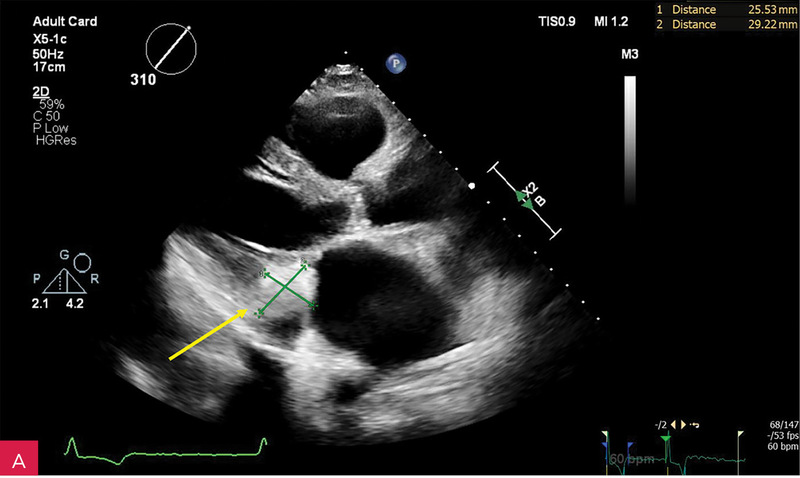

Rycina 2A, B. Zmiana u podstawy tylnego płatka mitralnego, obejmująca jego nasadę, a także fragment mięśnia ściany dolno-bocznej lewej komory w projekcji przymostkowej w osi długiej LAX (A) oraz w projekcji zmodyfikowanej, w której lepiej uwidoczniono hiperechogeniczną uwapnioną otoczkę zmiany oraz powodowany przez nią cień akustyczny (B)

Rycina 4A, B. Badanie echokardiograficzne przezklatkowe trójwymiarowe (3D TTE) – widok od strony lewej komory zastawki mitralnej i guzowatej zmiany o nierównej powierzchni (A) wraz z prezentacją zmiany w przekrojach wykonanych na podstawie 3D TTE (B)